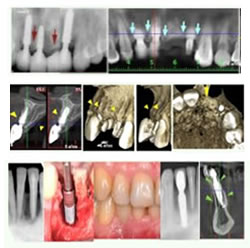

¿Cómo se colocan los implantes dentales?

Las restauraciones con los implantes dentales se llevan a cabo en dos fases. La primera fase consiste en la colocación quirúrgica del implante o los implantes en la mandíbula. Esto se lleva a cabo en el consultorio de su especialista implantológico. La colocación del implante es muy precisa, una vez en su sitio el tejido de la encía cubre el implante por un periodo curativo de tres a seis meses. Durante este tiempo el implante se une permanentemente al hueso.

La segunda fase consiste en la construcción del diente o dientes de remplazo (prótesis). Cuando el periodo de curación haya terminado, su dentista descubrirá la parte superior del implante dental usando un procedimiento rápido y sencillo. Entonces, usará el implante como la base sólida para restaurar sus dientes.

Mientras evolucionaban estas técnicas, paralelamente se producía un desarrollo evolutivo en los métodos de diagnóstico bucal, como la tomografía odontológica Cone Beam.

Finalmente, en estos años asistimos a la simplificación de técnicas y procedimientos a través del uso de implantes de última generación, cuya geometría o morfología y tipo de superficie permiten lograr resultados clínicos de gran calidad estética y funcional.